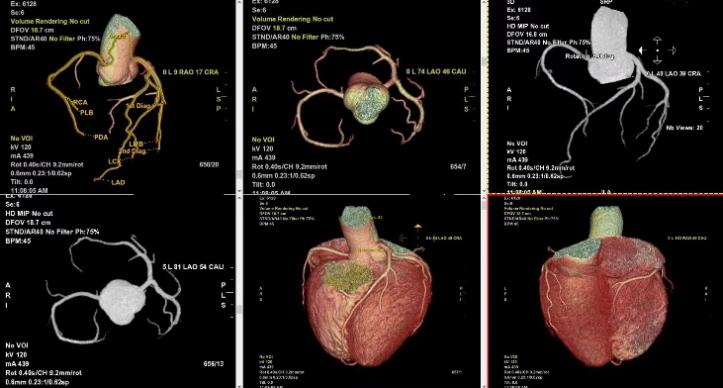

我们的服务项目涵盖了全身各部位的影像检查,包括但不限于:头部、颈部、胸部、腹部、盆腔、四肢等部位的CT、MRI、DR等检查。我们还提供特殊的影像检查服务,如血管造影、MR多功能成像等。例如:

血管造影: